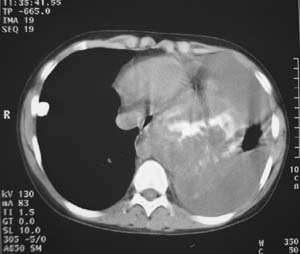

女性,17岁,一年前因股骨病变截肢,现胸憋。

左肺巨大肿块,内散在斑点状高密度骨化影,右肺见多发结节灶,双侧胸膜局限性增厚。有骨肉瘤病史,支持骨肉瘤手术后转移。